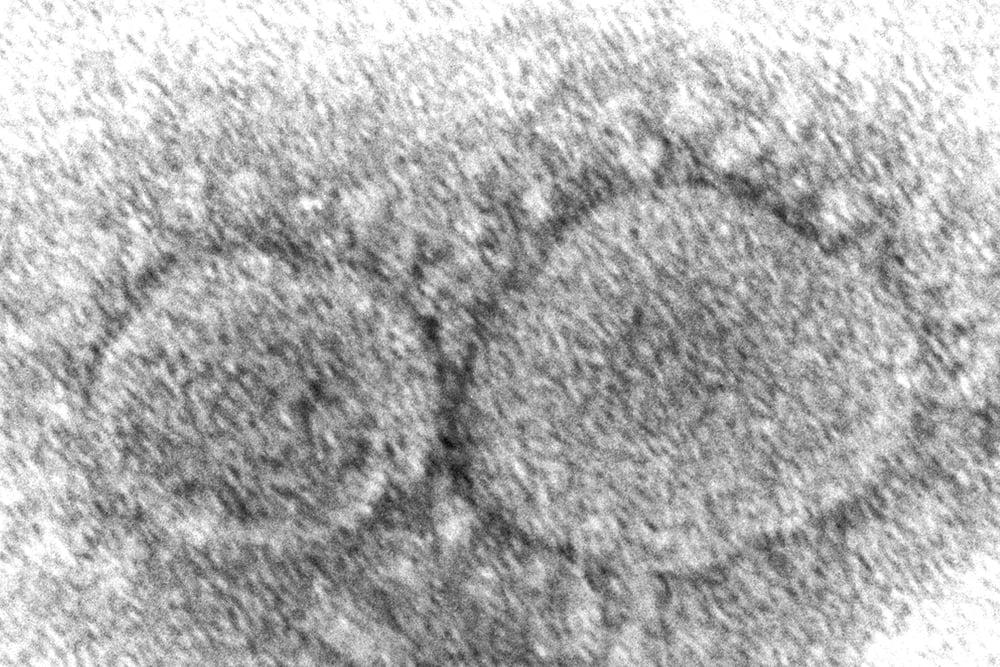

coronavirus

WHO downgrades COVID pandemic, says it’s no longer global emergency